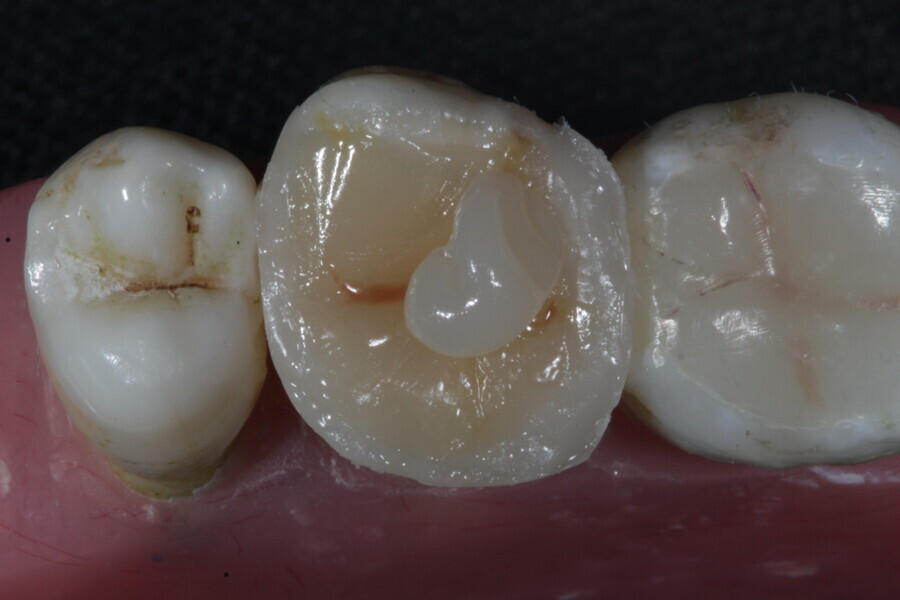

The second step focuses on reinforcing the restoration through careful fibre and FRC selection and placement. Tooth preparation should involve minimal removal of tooth structure to preserve as much natural tooth as possible in preparing the cavity for the restoration. Fibres or layers of FRC (flowable, paste, cube, etc.) are then strategically placed within the prepared tooth and composite material to reinforce areas susceptible to high stress and occlusal forces based on occlusal contact mapping. This strategic selection and placement of fibres and layers of FRC is crucial for enhancing the strength and longevity of the restoration.

The third step is to restore the tooth to its natural form, function and aesthetics. Composite resin, along with fibres or fibre-reinforced flowable or fibre-reinforced dentine substitute materials, is carefully applied to the prepared tooth structure. A layering technique is often used to ensure proper adhesion and integration of the reinforced materials with the composite material, enhancing the overall strength and functionality of the restoration. The composite resin is then polymerised using a curing light, ensuring that the materials are securely bonded within the restoration and providing a stable and long-lasting result. During this restorative process, the clinician should take special care not to expose fibres or FRC layers to the oral environment, as this can cause tissue irritation and water absorption by the materials in the long run. Therefore, the final layers of the restoration should always be a suitable aesthetic conventional composite resin.

1. direct restoration using a fibre-reinforced flowable composite and membrane cube after endodontic treatment (Figs. 21–35); and